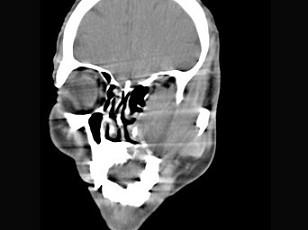

问题 男,65岁,左眼球突出近一年,鼻涕带血,面颊部隆起,同时面颊部有麻木感,CT检查如图,最可能诊断为 ( )

选项 A、上颌窦癌 B、骨肉瘤 C、上颌窦血管瘤 D、上颌窦囊肿 E、上颌窦息肉

答案 A